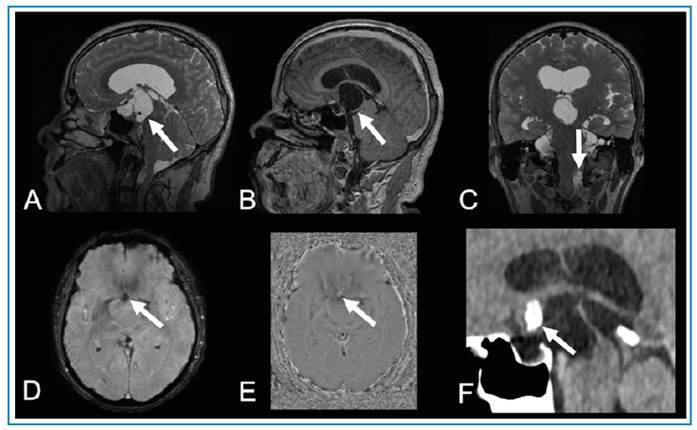

Racemose neurocysticercosis mimicking craniopharyngioma.